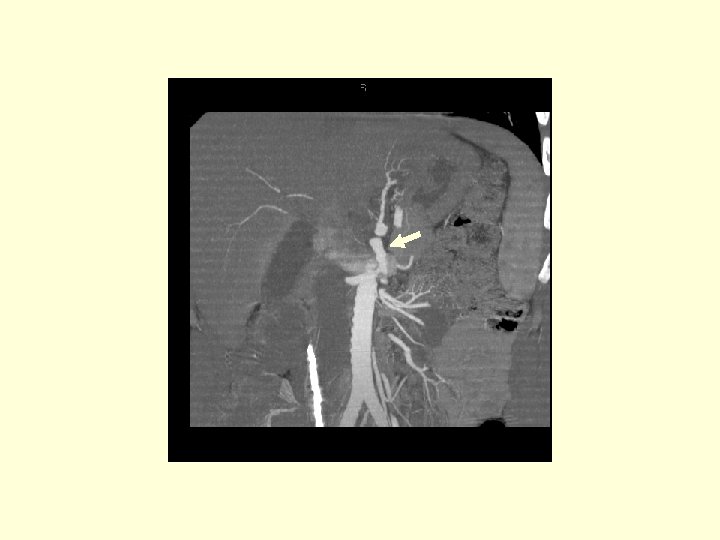

This is a 3 D image showing the branches of the SMA.

This is another 3 D image showing the vasculature of the SMA. Click through the next 20 frames to rotate the image.